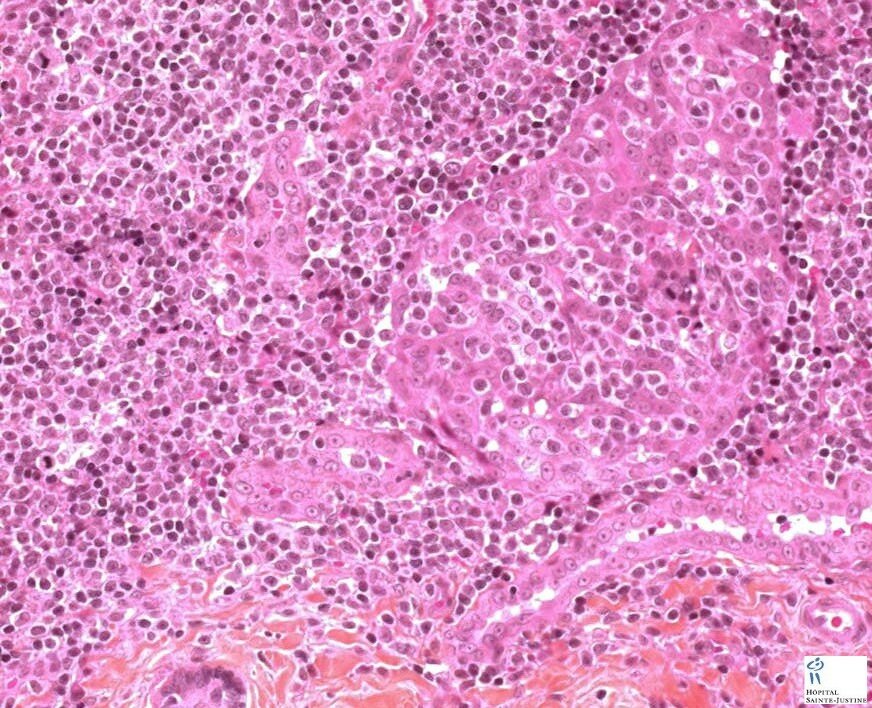

Atypical salivary lymphoid hyperplasia